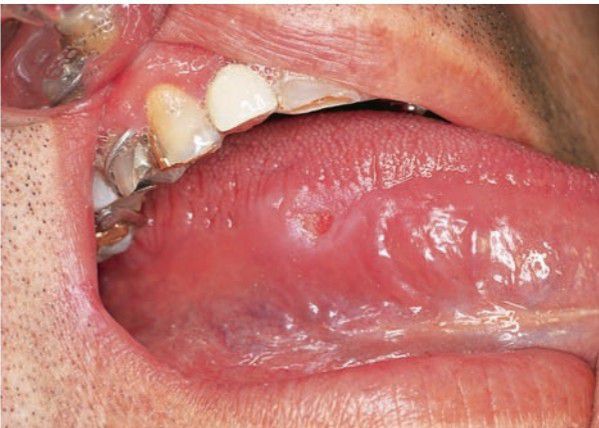

Chronic traumatic ulcer

Painful ulcer covered by yellow fibrin membrane; diagnosis usually evident from appearance when combined with history;